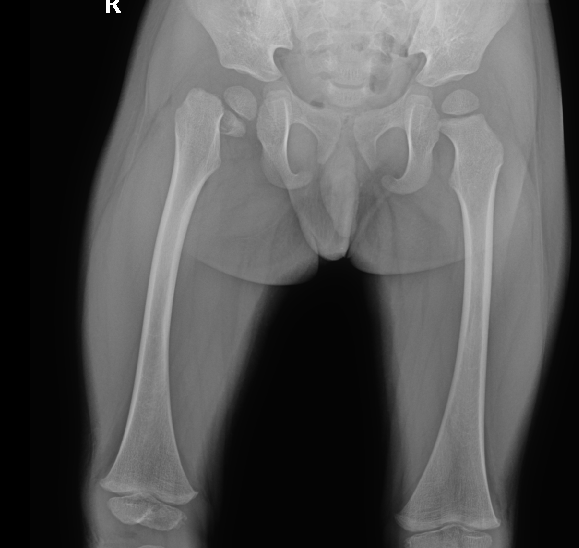

影像资料:

DR提示:右侧股骨颈骨折,断端错位,右股骨干上提,颈干角缩小,右股骨干未见明显异常,双侧髋关节关系未见明显异常,余无特殊。

股骨颈骨折,骨折端移位。

此病例诊断为股骨颈骨折不够准确,一定要仔细查阅患者X光片。周主任认为此病例诊断为股骨头骨骺分离更确切,伴有半脱位。